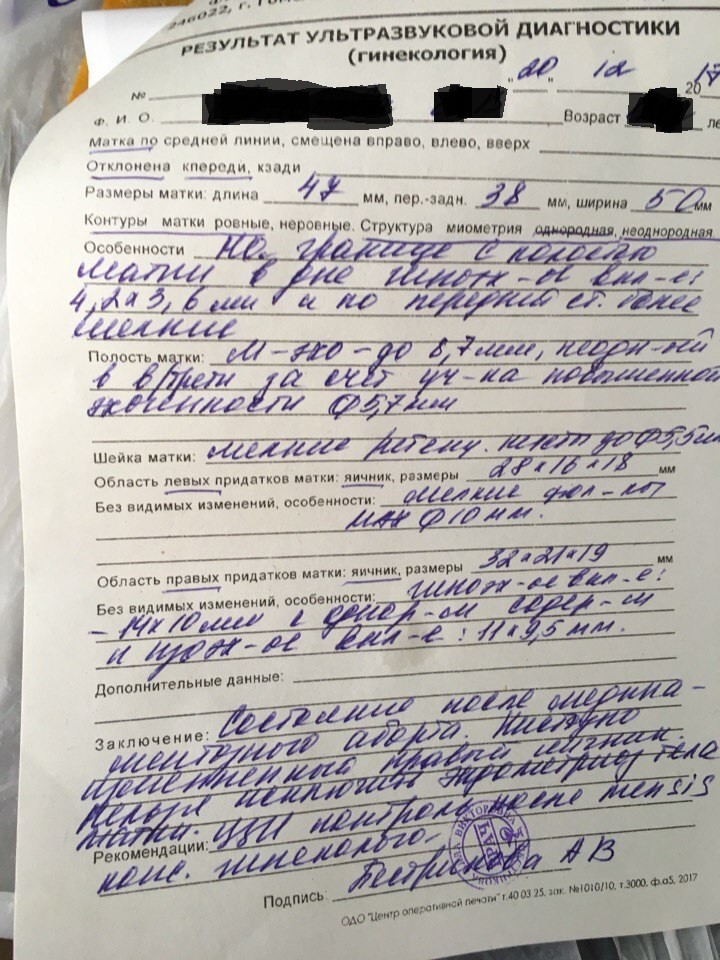

Медицина и диагностика: Инвазивный пузырный занос на УЗИ

Раздел: Альбом идей